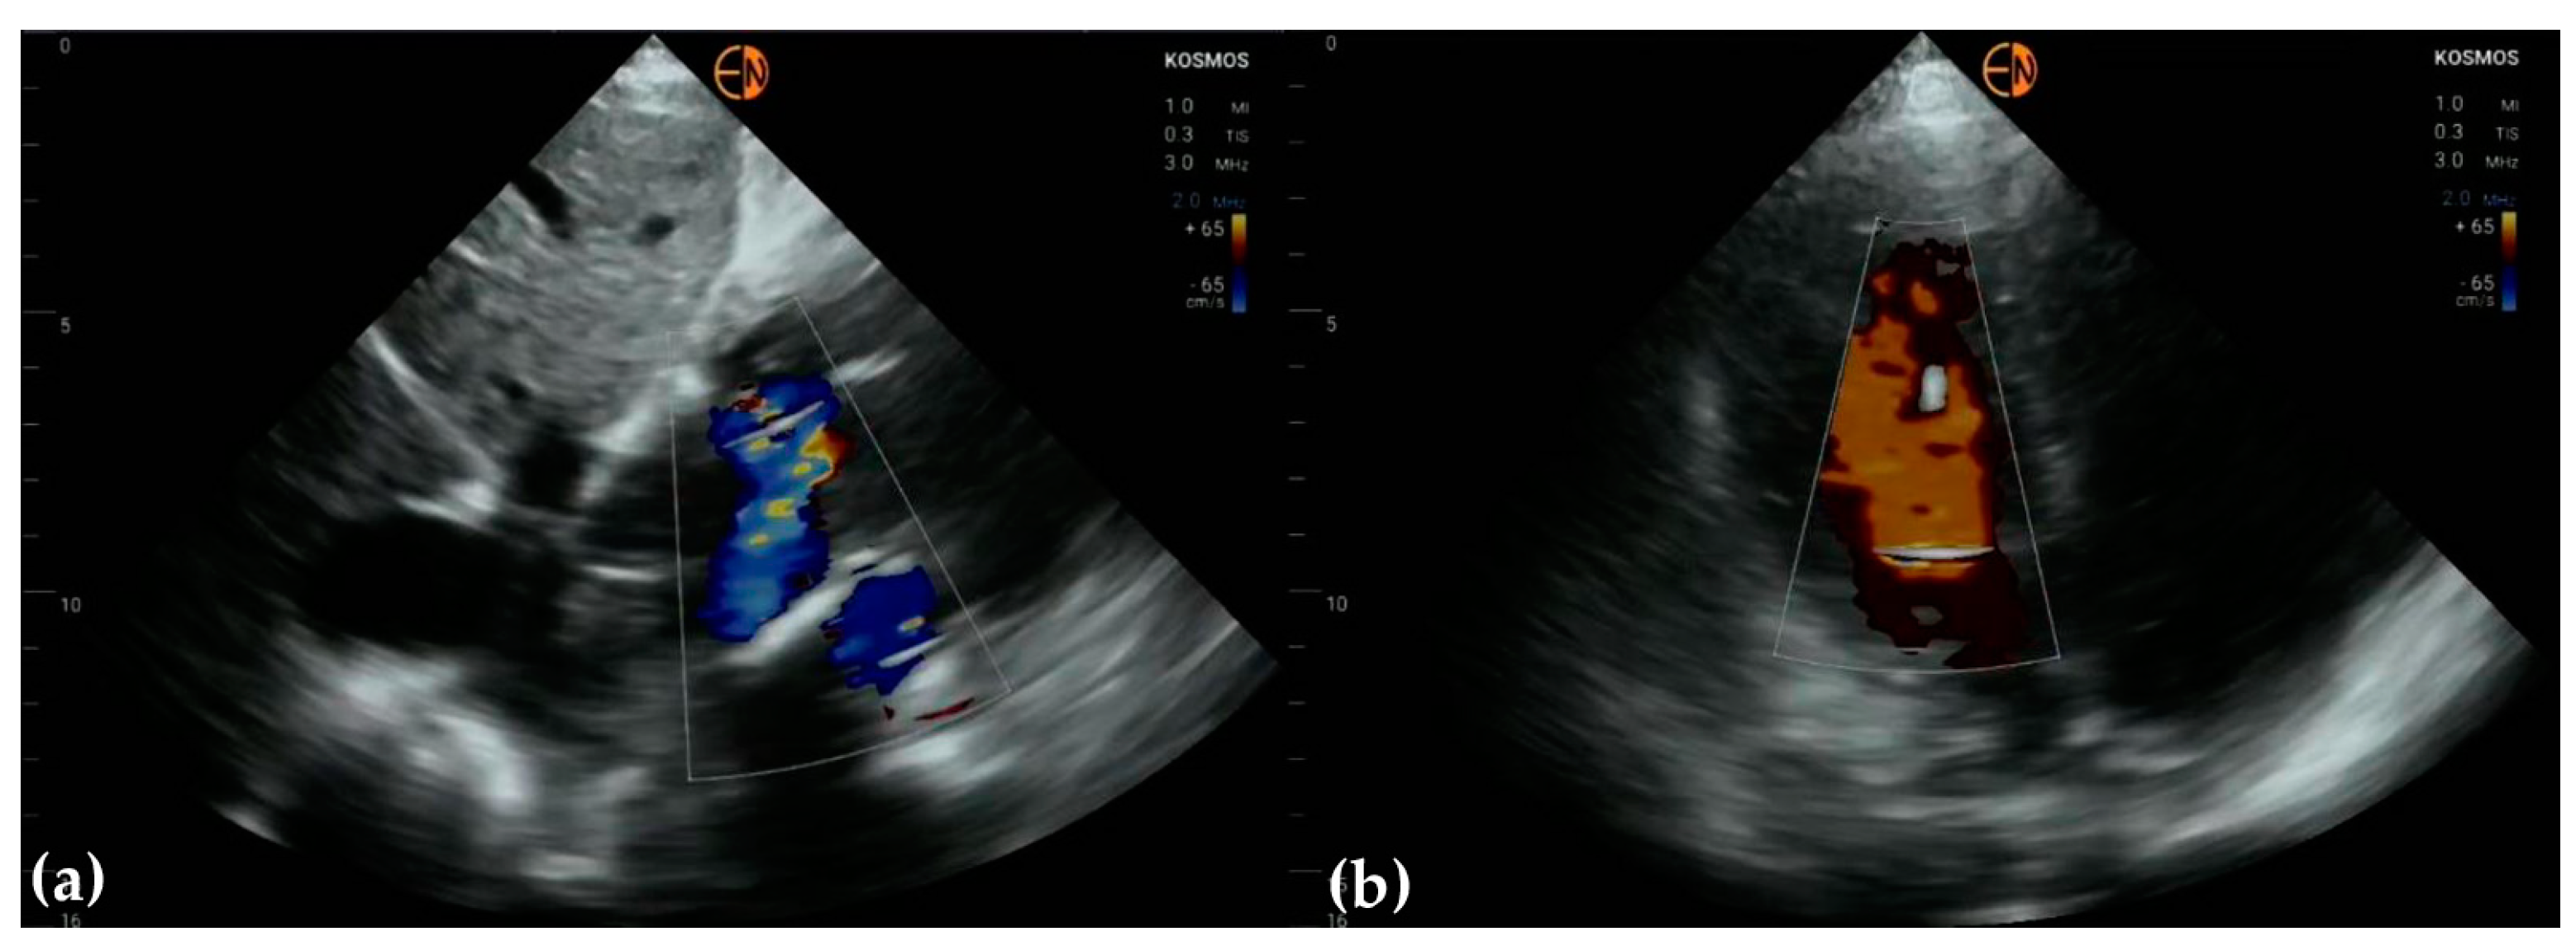

3.3. Valvular Stenosis and Regurgitation

3.4. Other Findings